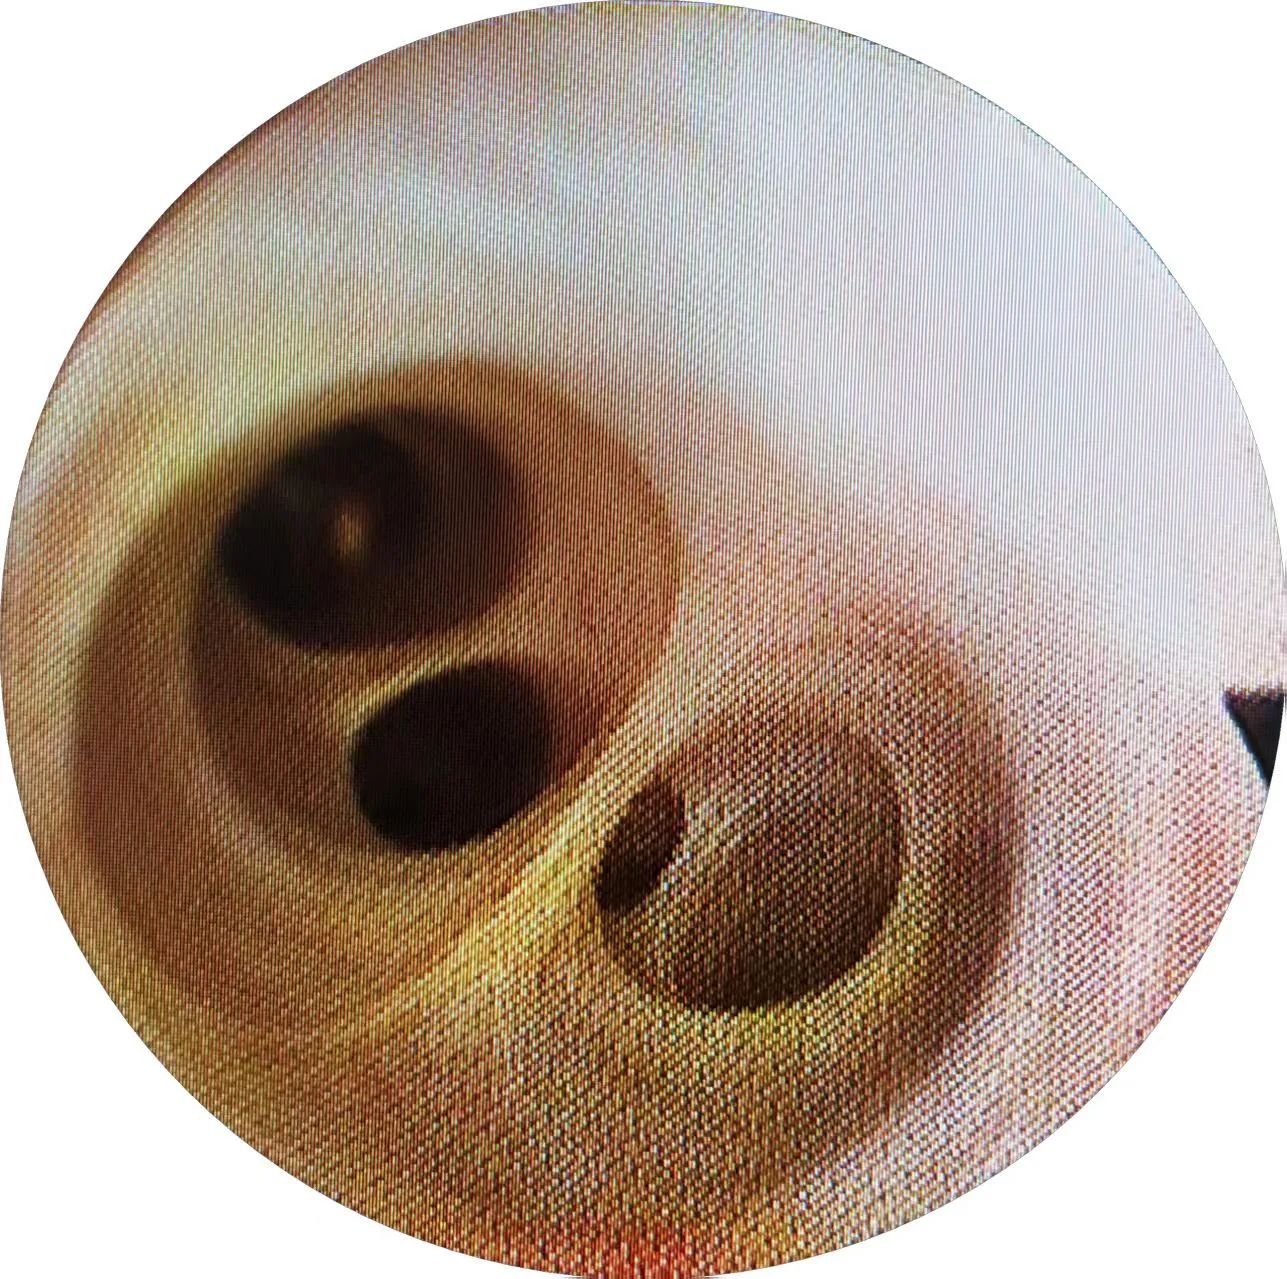

而胆道镜的纤细镜身能灵活深入胆管,高分辨率图像将结石、息肉等病灶纤毫毕现。配合取石网篮,它就像“绣花针”般精准抓取结石,让隐匿在胆道中的“定时炸弹”无处遁形。这两件“利器”宛如武侠小说中的“慧眼神通”一样,让隐藏的敌人显露无遗。

△该图片非案例提及

△该图片非案例提及